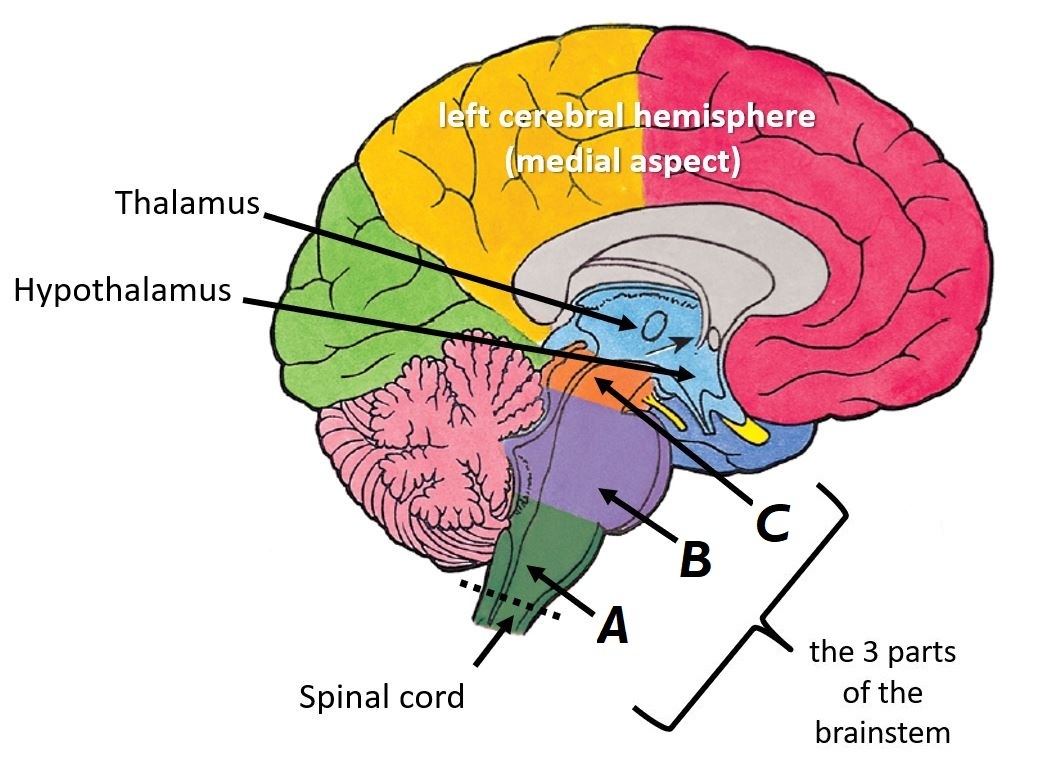

Name the parts of the brainstem A, B and C

A - Medulla oblongata

B - Pons

C - Midbrain